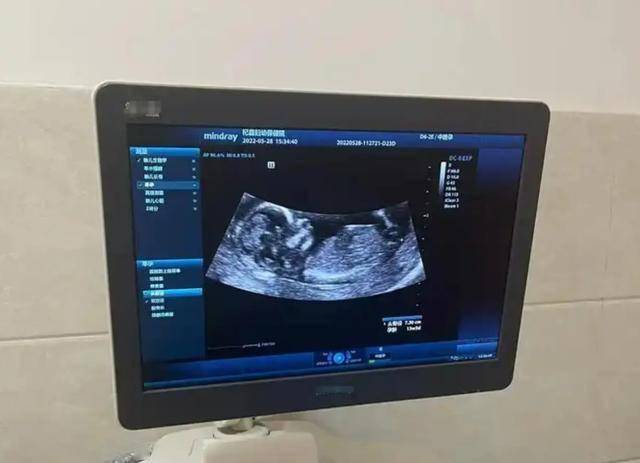

定期做颈部B超,35岁后每年一次为宜

甲状腺B超是发现早期癌变最便捷有效的方式。

中国抗癌协会建议:35岁以上人群,尤其是女性,每年进行一次甲状腺B超筛查。

对于曾患甲状腺结节或家族有甲癌病史者,应每半年复查一次。